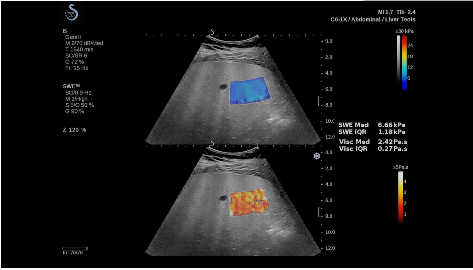

法國聲科影像(SuperSonic Imagine,SSI. Euroniex:FR0010526814)近日發(fā)表公告,宣布其研發(fā)的新一代“極速”超聲成像平臺(UltraFast Imaging),首次實現(xiàn)了肝臟的多項超聲定量評估新指標(biāo)同步檢測,包括:Att PLUS,SSp PLUS和Vi PLUS等,基本涵蓋肝臟相關(guān)病理變化指征的如纖維化、脂肪變、炎癥等。據(jù)悉,此多項新技術(shù)新將搭載于新Aixplorer系列E超系統(tǒng)。

該公司首席執(zhí)行官(CEO)Michèle Lesieur女士介紹:“慢性肝病是危害公共健康的重要疾病,并呈逐年上升趨勢。目前,全世界約有8.44億人正在受到這種慢性疾病的折磨。2017年,我們已經(jīng)研發(fā)出了能夠有效輔助肝病臨床處理的部分早期診斷工具,這成為無創(chuàng)、準(zhǔn)確評估慢性肝病嚴(yán)重程度的里程碑之一。與眾不同的是,此次的全面化技術(shù)群,由于相關(guān)定量測量技術(shù)都是基于超聲可視化圖像為基礎(chǔ),因此有可能幫助臨床醫(yī)生更高效快速地完成日常診斷治療的完整流程”。

E超相關(guān)技術(shù)已被多項多中心大樣本研究證實對于肝纖維化無創(chuàng)評估有重要意義,同時也可全面應(yīng)用于乳腺、甲狀腺、肝臟、前列腺、肌骨、婦科等全身各組織器官的定量評估和鑒別診斷。在慢性肝臟方面,聲科E超的肝臟相關(guān)定量診斷技術(shù)集,于2018年獲得美國FDA認(rèn)證,成為FDA歷史上首次獲批的單病種超聲全面定量解決方案。